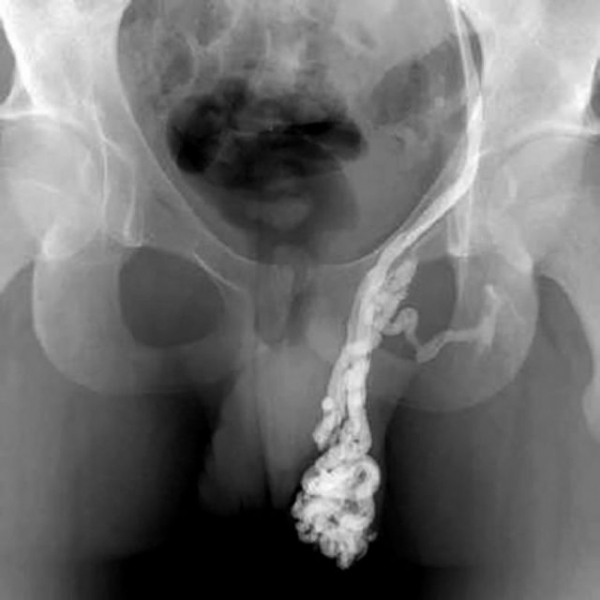

На снимке видно сильное расширение вен, при котором показано проведение операции Мармара

Интересно, что более чем в 90% случаев варикоцеле носит левосторонний характер. Правостороннее или двустороннее заболевание встречаются редко. Специалисты объясняют это патологией, в результате которой почечная вена впадает в яичковую. Симптомы зависят не столько от объема увеличенных вен и сосудов, сколько от степени повреждения.

Чаще всего варикоцеле бывает односторонним, причём развивается с левой стороны. Если варикозное расширение вен обнаружено в двух яичках, то это может свидетельствовать о серьёзных патологиях почек и их сосудов.